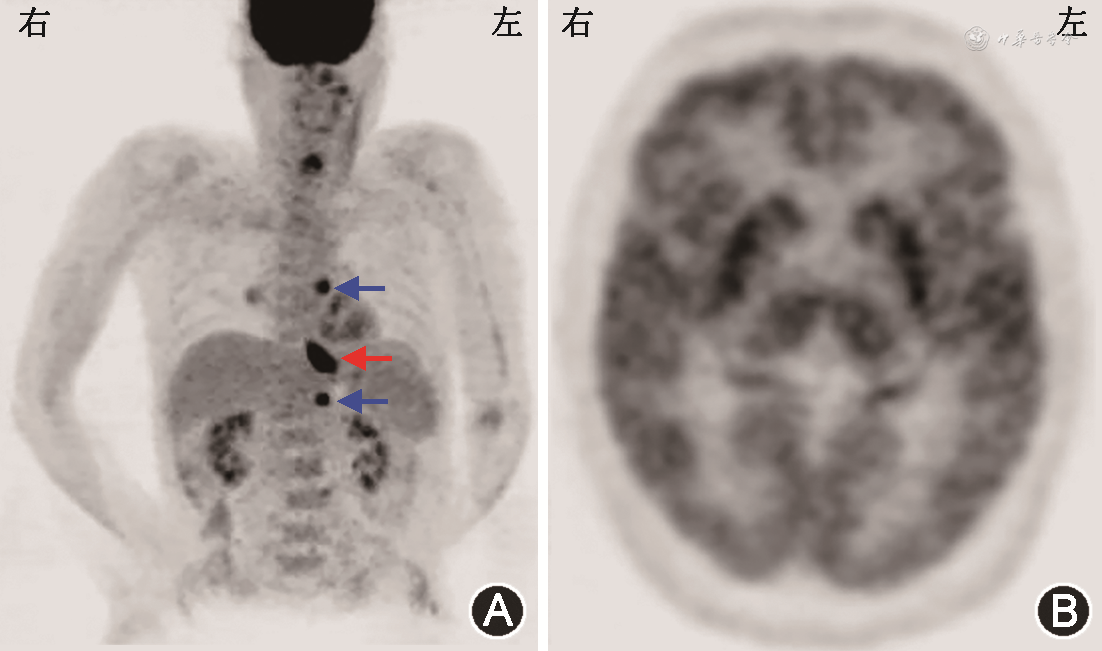

患者入院后完善胸、腹及盆腔CT平扫未见肿瘤性病变。复查腰椎穿刺(表1),脑脊液炎性反应较半个月前明显减轻;血及脑脊液抗两性蛋白抗体阳性,血及脑脊液抗CV2/CRMP5、Ma2、Hu、Yo、Ri抗体均阴性。9月1日行氟脱氧葡萄糖正电子发射体层摄影(FDG-PET;图1)示食管下段近贲门代谢增高灶,范围约2.7 cm × 2.1 cm,最大标准化摄取值(maximum standardized uptake value,SUVmax)14.1,恶性病变可能性大,伴T7水平食管左旁、肝胃间隙、上腹部腹膜后淋巴结转移,最大者短径约0.8 cm,SUVmax 7.3,建议行胃镜检查明确病理;双侧枕叶及小脑代谢减低,双侧颞叶内侧代谢不均匀稍增高,双侧基底节及丘脑代谢增高,脑干代谢不均匀稍增高,符合自身免疫性脑炎表现。9月9日胃镜(图2)示食管下段近贲门处后壁侧小孔样改变,局部无脓液溢出、黏膜稍充血、窄带成像下尚可,取活组织检查(活检)组织1块,质软。病理回报(图3)食管下段黏膜下见小团异型小蓝圆细胞浸润,结合免疫组织化学检查结果,符合神经内分泌癌(小细胞性)。

抗两性蛋白抗体阳性患者约80%合并恶性肿瘤,主要为小细胞肺癌和乳腺癌。既往报道的其他合并肿瘤还包括黑色素瘤、非小细胞肺癌、胃癌、食管癌、卵巢癌和宫颈癌,但均仅有1、2例患者的报道[2,8]。我科在2016年曾对13例抗两性蛋白抗体相关副肿瘤神经综合征患者的总结发现,共6例患者存在恶性肿瘤,其中5例为小细胞肺癌,1例为乳腺癌。食管小细胞性神经内分泌癌是一种罕见肿瘤,约占食管恶性肿瘤的0.5%~2.8%[9]。我们仅检索到1例抗两性蛋白抗体阳性患者合并食管癌的报道,其具体病理类型不详[2]。抗Hu抗体相关副肿瘤神经综合征患者中曾有食管小细胞癌的病例报道[10, 11]。本例患者胸、腹及盆腔CT并未发现肿瘤,胃镜下亦未见典型的肿瘤病灶,FDG-PET对其肿瘤的发现、活检定位均起到了重要作用。在神经内分泌肿瘤的病理诊断中,常用的反映神经内分泌和神经分化的标志物包括突触素(synaptophysin)、嗜铬粒蛋白和CD56。Ki-67标记指数则在神经内分泌肿瘤的分级中起重要作用,Ki-67指数>20%提示高级别肿瘤。本例患者病理HE染色见异型小蓝圆细胞浸润,免疫组织化学突触素部分阳性,CD56阳性,Ki-67指数90%,符合神经内分泌癌(小细胞性)诊断。考虑肺外小细胞癌与小细胞肺癌病理学上的一致性,符合2021年PNS诊断标准中与抗体一致的肿瘤[3]。